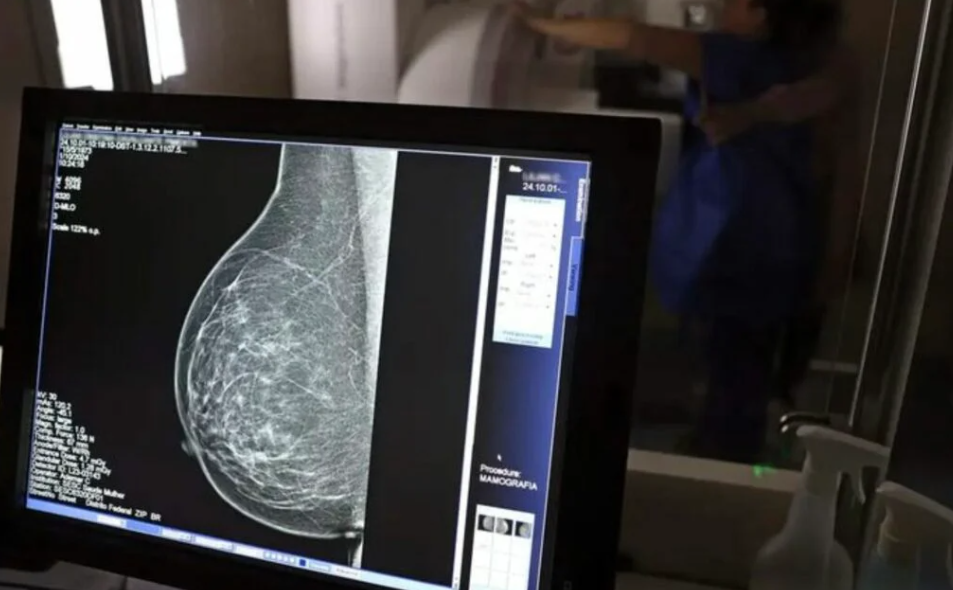

No mês do Outubro Rosa, o Ministério da Saúde recebe o primeiro lote do Trastuzumabe Entansina, medicamento de última geração incorporado ao SUS para o tratamento do câncer de mama HER2-positivo, uma forma agressiva da doença que estimula o crescimento das células tumorais. A primeira remessa, com 11.978 unidades (6.206 de 100 mg e 5.772 de 160 mg), chegou nesta segunda-feira (13) ao almoxarifado do Aeroporto Internacional de Guarulhos (SP).

“É um avanço gigantesco para a oncologia nacional, com o primeiro protocolo clínico voltado a esse tratamento. Trata-se de uma medicação muito esperada pela nossa população, que poderá reduzir em até 50% a mortalidade das pacientes com câncer de mama do tipo HER2 positivo. É uma grande vitória para a saúde pública e para o povo brasileiro”, afirmou o diretor do Departamento de Atenção ao Câncer do Ministério da Saúde, José Barreto.